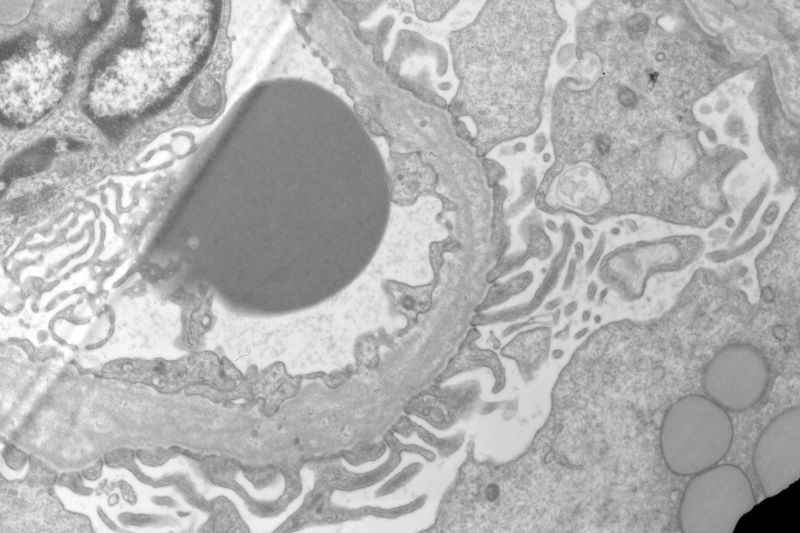

Sixty old man with proteinuria and hematuria

Here are the additional EM photos with high magnification:

Picture 2 you fisrt posting showed a lot of foamy cells and some things like HP  in a tubular cavity in the centre of picture. About picture 7, i can see one capillary loop and its endothelial cell, i'm doute of  like a tadpole someting different in the capillary cavity , can you tell me, thank you very much.

Yes, I agree with your observation that there are a lot of foamy cells. The most impressive change is the lamination or splitting of the glomerular basement membrane.

In the photo #7, there are three platelets in the capillary lumen. I don't know their significance.

Thank you,to combine the splitting of the glomerular basement membrane with a lot of foamy cells infiltration, I first take into account Alport Syndrome, but the age of the patient is too old, so Alport Syndrome seems unlikely. Under LM, the glomerulosclerosis and tubular atrophy/interstitial fibrosis. Please comment, thank you

The patient has a long history of "chronic kidney disease". Initially, he did not tell the nephrologist that he started to have kidney disease decades ago. Given the characteristic ultrastructural changes, Alport's syndrome is suggested.